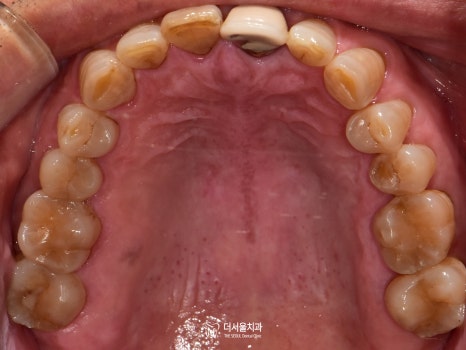

자, 우선 현재 상황을 확인해 봐야겠죠?

더 서울에서 정확한 진단을 위해

엑스레이 촬영을 진행한 결과,

하악 우측 잔존 어금니는 심한 충치로 인해

병소가 치수까지 감염되어 있었습니다.

빠져있는 아래 어금니 세 곳에

인공치를 심기로 했었는데요.

세 곳 모두 주변 조직 및 인접치와의 관계를

각각 파악하여 최적의 식립로를 설정했습니다.